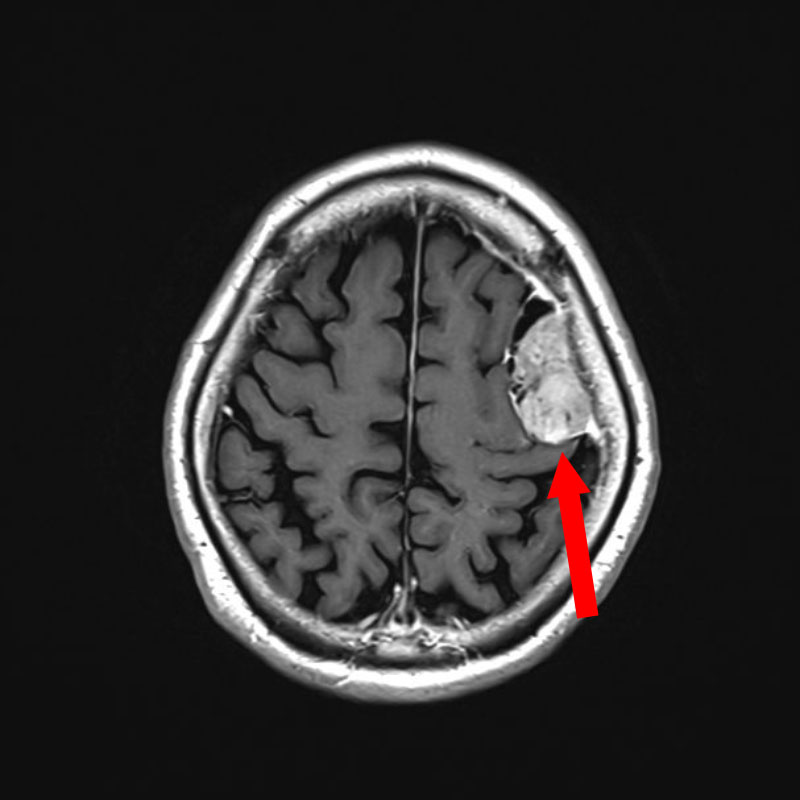

No.’25_108 手術前1

No.’25_108 手術前2